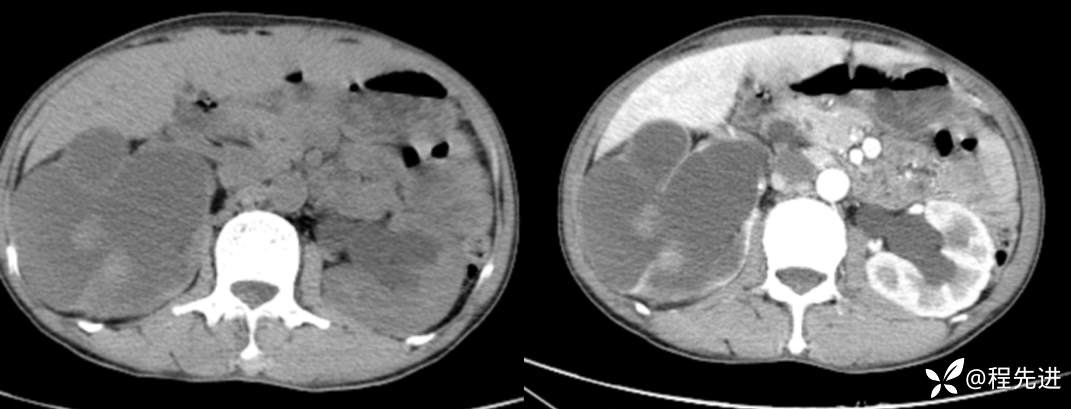

CT平扫+增强

来张特定(左平扫,中动脉期,右静脉期)